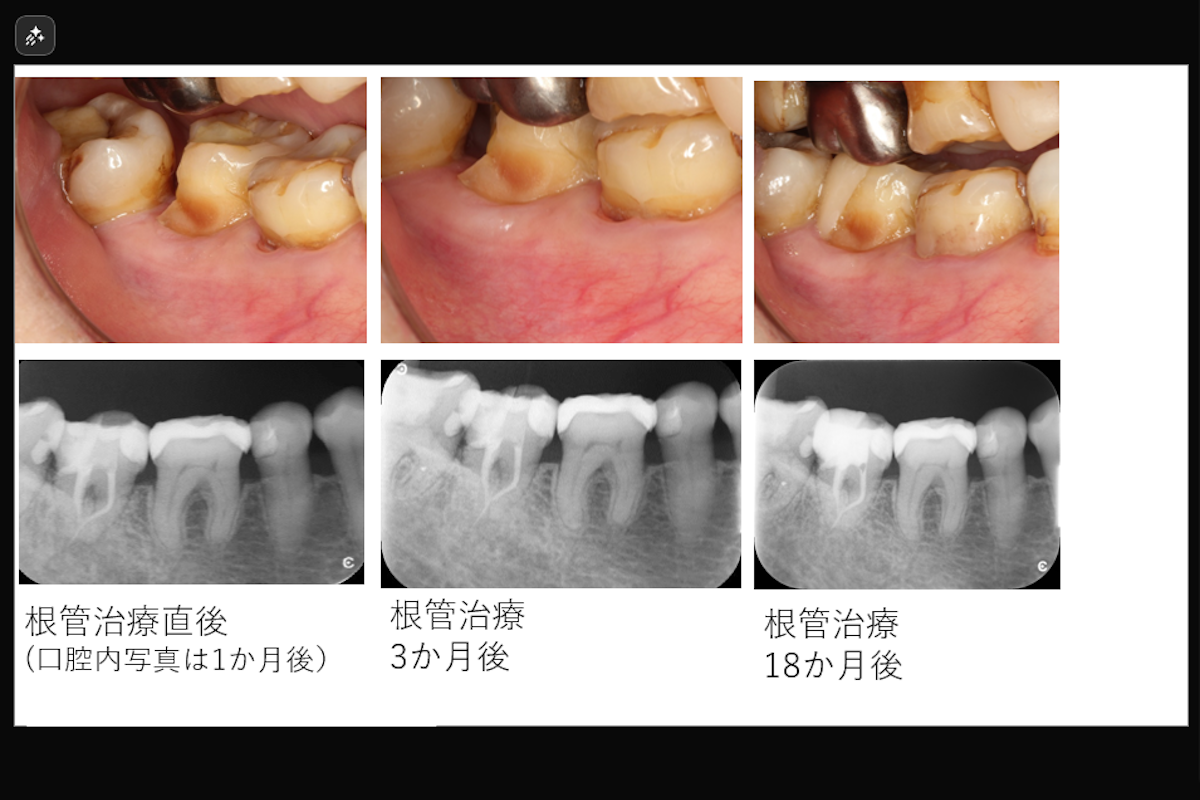

- 治療期間: 約1か月

- 治療回数 1回

- 治療費目安: およそ16万円 (根管治療)

- 根管治療(レーザーを用いた根管洗浄)

- 治療のリスク: 残存歯質の厚みによって歯根破折のリスク、経過によっては外科的歯内療法が必要